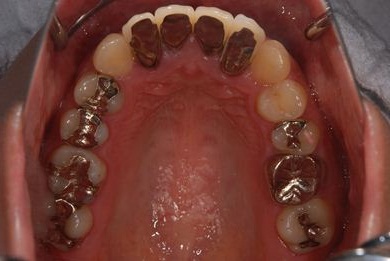

治療前

• 治療前

治療内容 オールセラミッククラウン4本(オールセラミック用土台4本)、歯肉歯槽骨整形手術